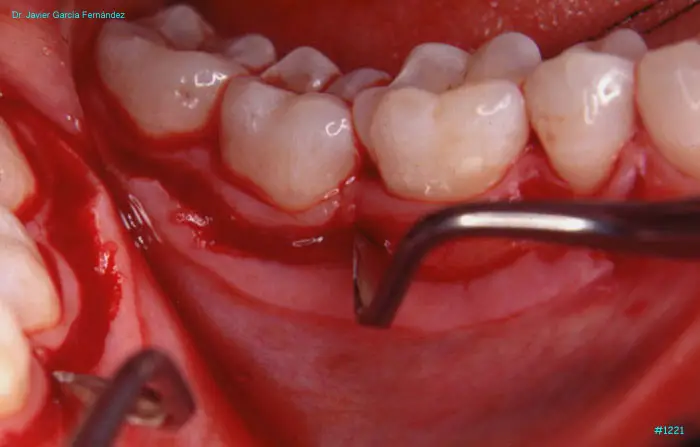

Atlas of Surgical Techniques in Periodontics. Chapter III. Atlas de Técnicas Quirúrgicas en Periodoncia